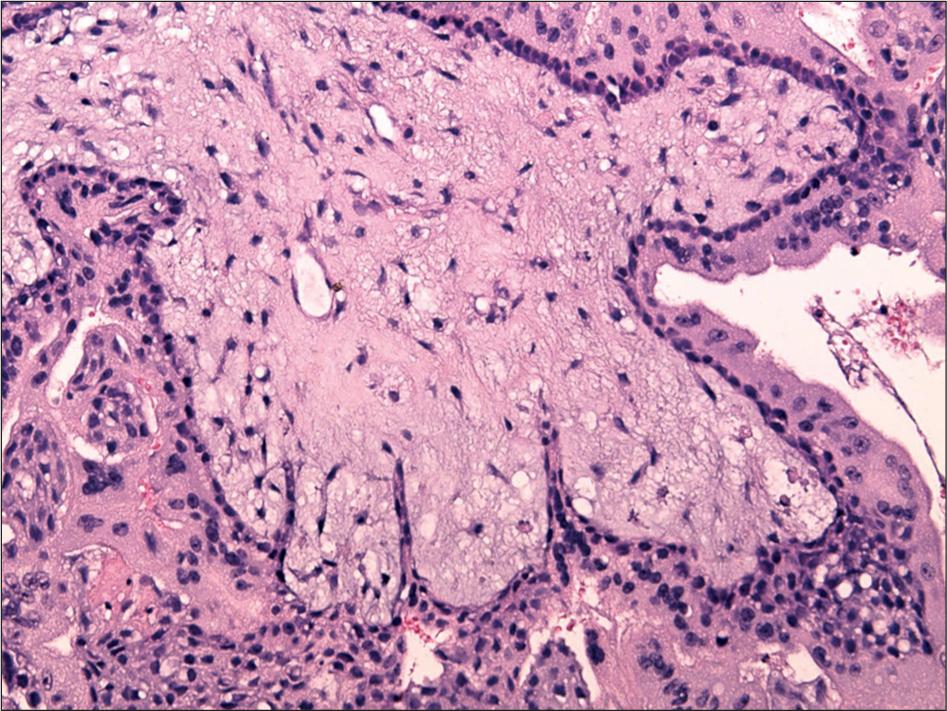

Histopathological characteristics of complete mole_

| Complete Mole | Absent or | Complete |

|---|---|---|

| Heterogenous population of villi | absent | 0 (0.0) |

| Circumferential trophoblastic proliferation | absent | 1 (12.5) |

| Cytotrophoblastic proliferation | absent | 3 (37.5) |

| Nuclear atypia | absent | 0 (0.0) |

| Karyorrhectic stromal debris | absent | 6 (75 0) |